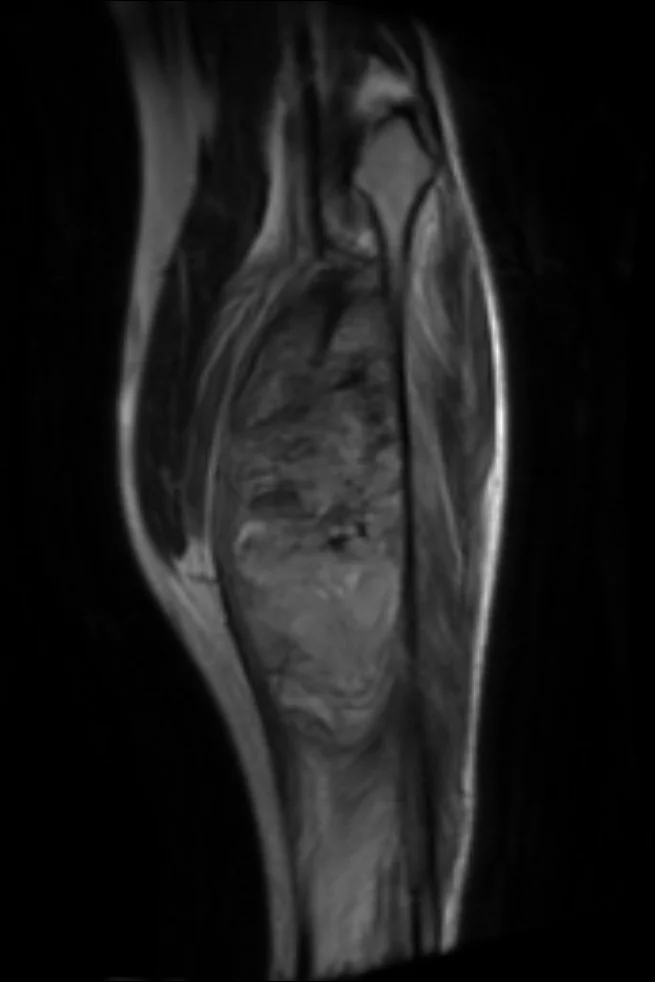

If you have never seen a Sacrococcygeal Teratoma or Vein of Galen Malformation before, myFRCR is the place. If you want to gain confidence in diagnosing the various bone malignancies, such as a Clear Cell Chondrosarcoma versus a Chondroblastoma, myFRCR will help you. If you just want to pass the FRCR exam comfortably, myFRCR will give you the best possible chance at achieving your goal.

A similar depth of detail is given to MSK:

Master your FRCR 2B examination with authentic, expert-created content. Access 1,250+ short cases (2,000+ radiographs) across 50 packets, plus 600+ long cases (1,000+ cross-sectional images) in 100 packets. Every image is a full lossless DICOM at diagnostic workstation quality, following RCR display guidelines. No AI-generated content – all cases, questions, and answers are meticulously crafted by experienced radiologists.

Experience authentic FRCR 2B preparation with our professional DICOM viewer displaying full lossless images at diagnostic workstation quality. Access 1,250+ short cases and 600+ long cases – all created by expert radiologists with zero AI-generated content.

2,000+ radiographs and 1,000+ cross-sectional images in full lossless DICOM format.

Zero AI content – all cases created by expert consultant radiologists.